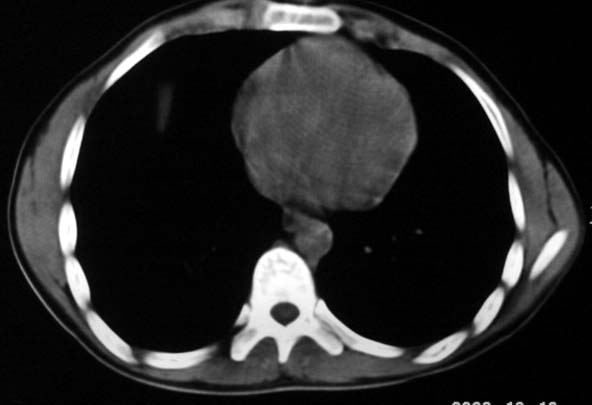

标题: CT5614:外伤病人男,20岁,右上腹痛.余肺野(-) [打印本页]

标题: CT5614:外伤病人男,20岁,右上腹痛.余肺野(-)

外伤病人男,20岁,右上腹痛,ct显示:右肺下叶后基地段见斑片状高密度影,密度不均,边界清,考虑1,右肺下叶肺挫伤;2,炎症。

其次,病灶较多并散布在右下肺底,纵肺比例明显小于50%,与膈肌以及后壁胸膜有轻度粘连。且其内密度不均匀,最大的那个结节影里面有较致密密度,胸椎旁似乎还有液平面。也就是说右下肺炎性改变可以肯定。